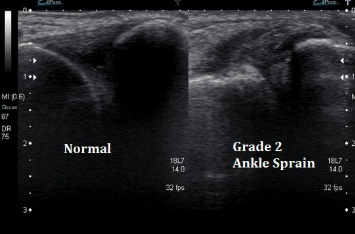

초음파·MRI: 인대 손상 및 파열 상태 정밀 확인.

♼ 손상 정도 구분

2도: 인대가 부분적으로 파열됨